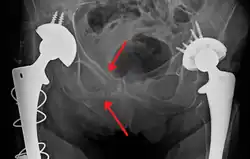

Trauma pélvico contuso

As causas mais comuns de trauma pélvico contuso são acidentes de veículos motorizados e quedas recorrentes, sendo comumente associadas a lesões traumáticas adicionais em outros locais.[28] Especificamente na pelve, as estruturas em risco incluem os ossos pélvicos, o fêmur proximal, os principais vasos sanguíneos (como as artérias ilíacas), o trato urinário, os órgãos reprodutivos e o reto.[29][28]

Uma das principais preocupações é o risco de fratura pélvica, que está associada a inumeráveis complicações, incluindo sangramento, danos à uretra e à bexiga e danos nervosos.[30] Se houver suspeita de trauma pélvico, os socorristas podem colocar um cinto de imobilização pélvico no paciente para estabilizar sua pelve e evitar mais danos a essas estruturas enquanto o mesmo é transportado para um hospital. Durante a avaliação de pacientes com trauma em um departamento de emergência, a estabilidade da pelve é normalmente avaliada pelo profissional de saúde para determinar se a fratura pode ter ocorrido. Os profissionais podem então decidir solicitar exames de imagem, como radiografia ou tomografia computadorizada, para detectar fraturas. No entanto, se houver suspeita de sangramento com risco de morte, o paciente deve passar por radiografia de pelve.[31] Após o tratamento inicial, as fraturas podem precisar ser tratadas cirurgicamente se forem significativas, enquanto outras menores podem cicatrizar sem a necessidade de intervenção cirúrgica.[28]

Uma preocupação com risco de morte é a hemorragia, que pode ser resultado de danos à aorta, artérias ilíacas ou veias da pelve, sendo a maioria dos sangramentos devido ao trauma pélvico proporcionada por lesões nas últimas.[30] Fluido (geralmente sangue) pode ser detectado na pelve por meio do ultrassom da ultrassonografia FAST, que geralmente é realizada após lesões traumáticas. Se um paciente parecer hemodinamicamente instável e não existir sangue evidente no exame FAST, pode haver preocupação com sangramento no espaço retroperitoneal, conhecido como hematoma retroperitoneal. Parar o sangramento pode exigir cirurgia endovascular ou cirurgia comum, dependendo da localização e da gravidade.[29]